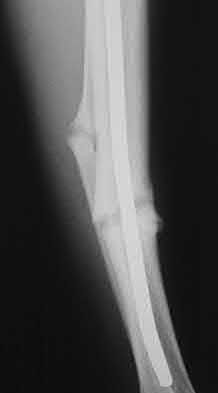

1005) Figure 48 shows the radiograph of a 17-year-old boy who sustained a gunshot wound to his forearm. There is a small entrance wound on the volar surface. The exit wound is dorsal and more than 15 cm in size, with loss of skin and an extensive amount of devitalized muscle hanging out of the wound. Vascular supply to the hand is excellent, the ulnar and median nerves are intact in the hand, but the radial sensory nerve function is absent. After repeated surgical

debridements of the wound and bone, definitive treatment for the fracture would most likely be which of the following?

Corrent answer: 2

The injury needs a very complex traumatic reconstruction. After repeat debridements, there will be a very long segmental loss of the radius, with a significant loss of skin and muscle covering the bone. Spanning external fixation represents a good temporary fixation tool but will not be a definitive solution. The preferred procedure is a vascularized fibular graft with associated skin flap from the lateral leg. This surgical option brings healthy vascularized bone and soft-tissue coverage into an area with significant bone and soft-tissue loss. Placement of large quantities of allograft material, especially strut allograft, is generally contraindicated in the setting of open fractures with soft-tissue compromise because of the risk of infection. Internal fixation and

massive cancellous autografting is usually limited to one defect of less than 5 cm with intact soft-tissue covering.